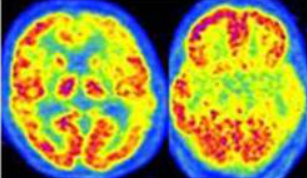

La PET-FDG nello studio e nell’identificazione dell’Alzheimer: guida completa alla diagnostica molecolare e alla caratterizzazione fenotipica

La comprensione della malattia di Alzheimer (AD) ha subito un’evoluzione paradigmatica negli ultimi decenni, passando da una diagnosi basata esclusivamente sull’osservazione clinica ex post a una caratterizzazione biologica in vivo supportata da biomarcatori avanzati. In questo contesto, la Tomografia ad Emissione di Positroni (PET) con il radiofarmaco 18F-fluorodeossiglucosio (18F-FDG) si è affermata come uno strumento…